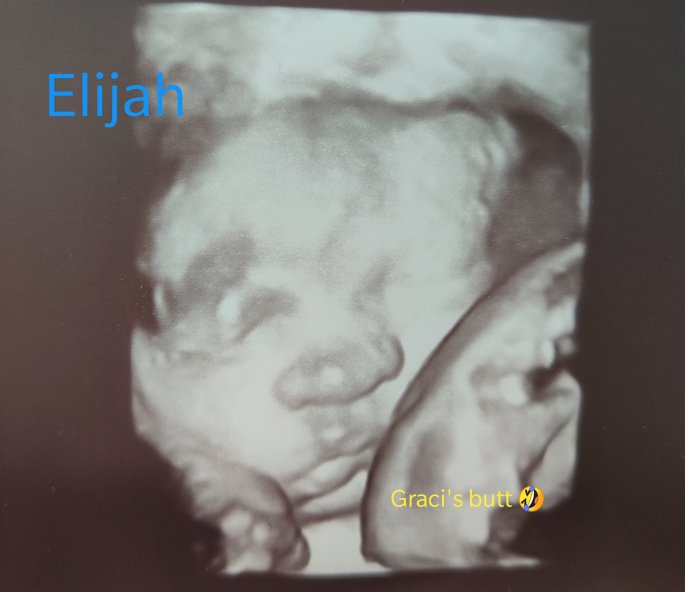

During this time I had a follow-up ultrasound done because the US tech at the hospital saw something they didn’t think was just right… With baby B the gap between the base of the neck and the lining of the sac was bigger than it is supposed to be. With the gap the size that it is, there is a 50% chance that there could be something wrong. Luckily a few weeks later I got the test results for the blood work and everything turned out ok with that. There were a few other tests that I needed to do, but in the end, everything turned out perfect!!

Having our babies in the NICU was hard emotionally. Going back and forth every day… then feeling like you are not there enough. Is hard. Then when Graci came home but Eli had to stay it was even harder. I couldn’t take Graci back up with me so unless I had a babysitter or Brett was home, I couldn’t go up there nor could Brett and I really go up there together. It was rough. Thankfully Eli was only in the NICU for a week longer than Graci.

Our Twinsies were born!!! FEB 20, 2021!!!!

I get into the surgery room and there are so many people in there. There is a full team for baby a. A full team for baby b and a full team for me. As soon as they get me all set up and in position they tell me with the next contraction I can push. It took two pushes and my lil boy came right out. He was born at 5:52pm and 4lb 14oz, 17 1/4″ long.

My lil girl had other plans. They broke her water and we had to wait for another 1/2 hour for her to get into position and come out. She was born at 6:25pm and 4lb 8.7oz 16 1/2″ long.

They both had to be taken to NICU. Elijah was there for 12days and Graci was there for 6days.